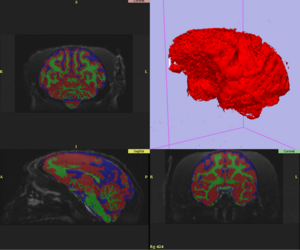

BRAINS.gif

PAR-05-057: BRAINS Morphology and Image Analysis

This project is a funded under a Continued Development and Maintenance of Software grant to PIs Vincent Magnotta, Hans Johnson, Jeremy Bockholt, and Nancy Andreasen at the University of Iowa. The goal of this project is to update the BRAINS image analysis software developed at the University of Iowa. More...